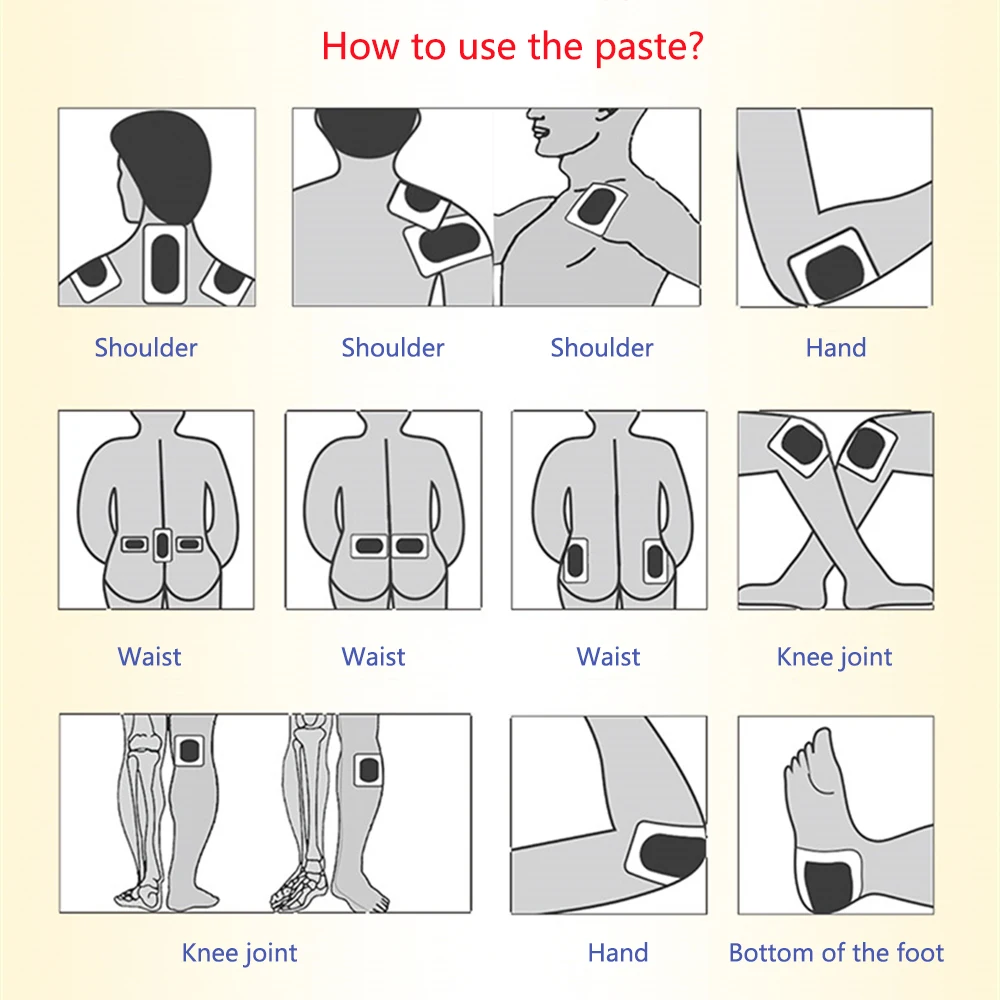

Scope of application: for pain caused by cervical pain, frozen shoulder, lumbar pain, knee joint and soft tissue injury. Precautions: The following conditions are disabled. Those who are allergic to this product, Skin ulcer, and wound, pregnant women, infant. ·Chinese Pain Relief Plaster is a flexible pain relieving...

Scope of application:

for pain caused by cervical pain, frozen shoulder, lumbar pain, knee joint and soft tissue injury.

·Felxible material with Medium Size suitable for relief back muscle pain, knee joint pain, frozen neck shoulders, wrist pain, arm fatigue, rheumatoid arthritis.

Direction:

Foot Skin Care,Assist treatment for cervical pain,shoulder periarthritis,lumbar muscle strain,lumbar disc herniationknee joint ache.

Foot Skin Care,Assist treatment for cervical pain,shoulder periarthritis,lumbar muscle strain,lumbar disc herniationknee joint ache.